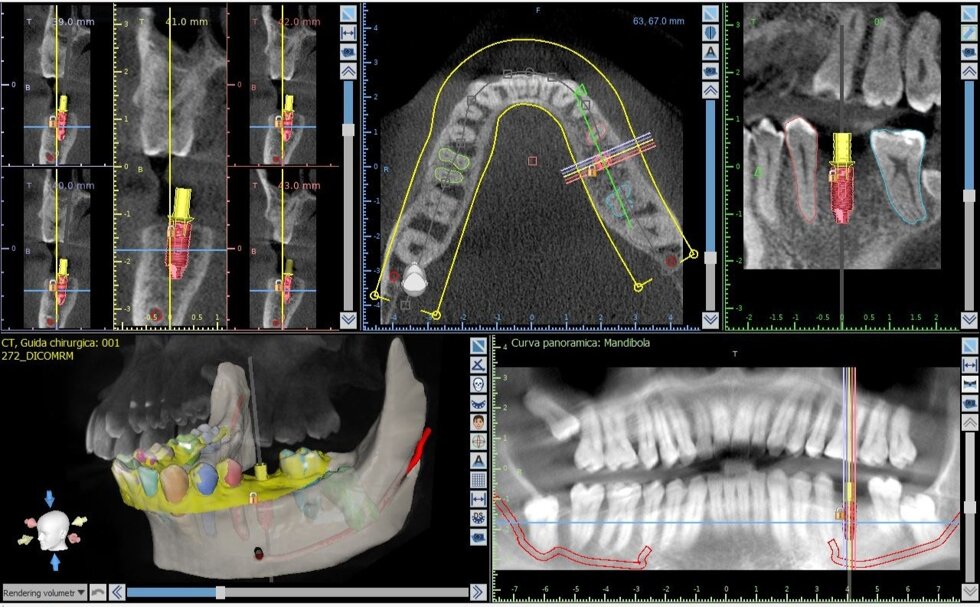

Il processo inizia con una tomografia computerizzata (CBCT), che fornisce un’immagine tridimensionale dettagliata delle arcate dentarie e delle strutture ossee. I dati vengono importati in software dedicati, dove il chirurgo può pianificare virtualmente l’intervento: scegliere la posizione, l’inclinazione e la profondità ottimali di ciascun impianto, valutando anche la densità ossea e la distanza da nervi o seni mascellari.

Una volta definito il piano chirurgico, si procede alla realizzazione di una dima chirurgica personalizzata, ottenuta tramite stampa 3D. Questa mascherina guida gli strumenti del chirurgo durante l’intervento, consentendo di inserire gli impianti nella posizione esatta prevista dal progetto digitale, senza necessità di ampie incisioni gengivali.